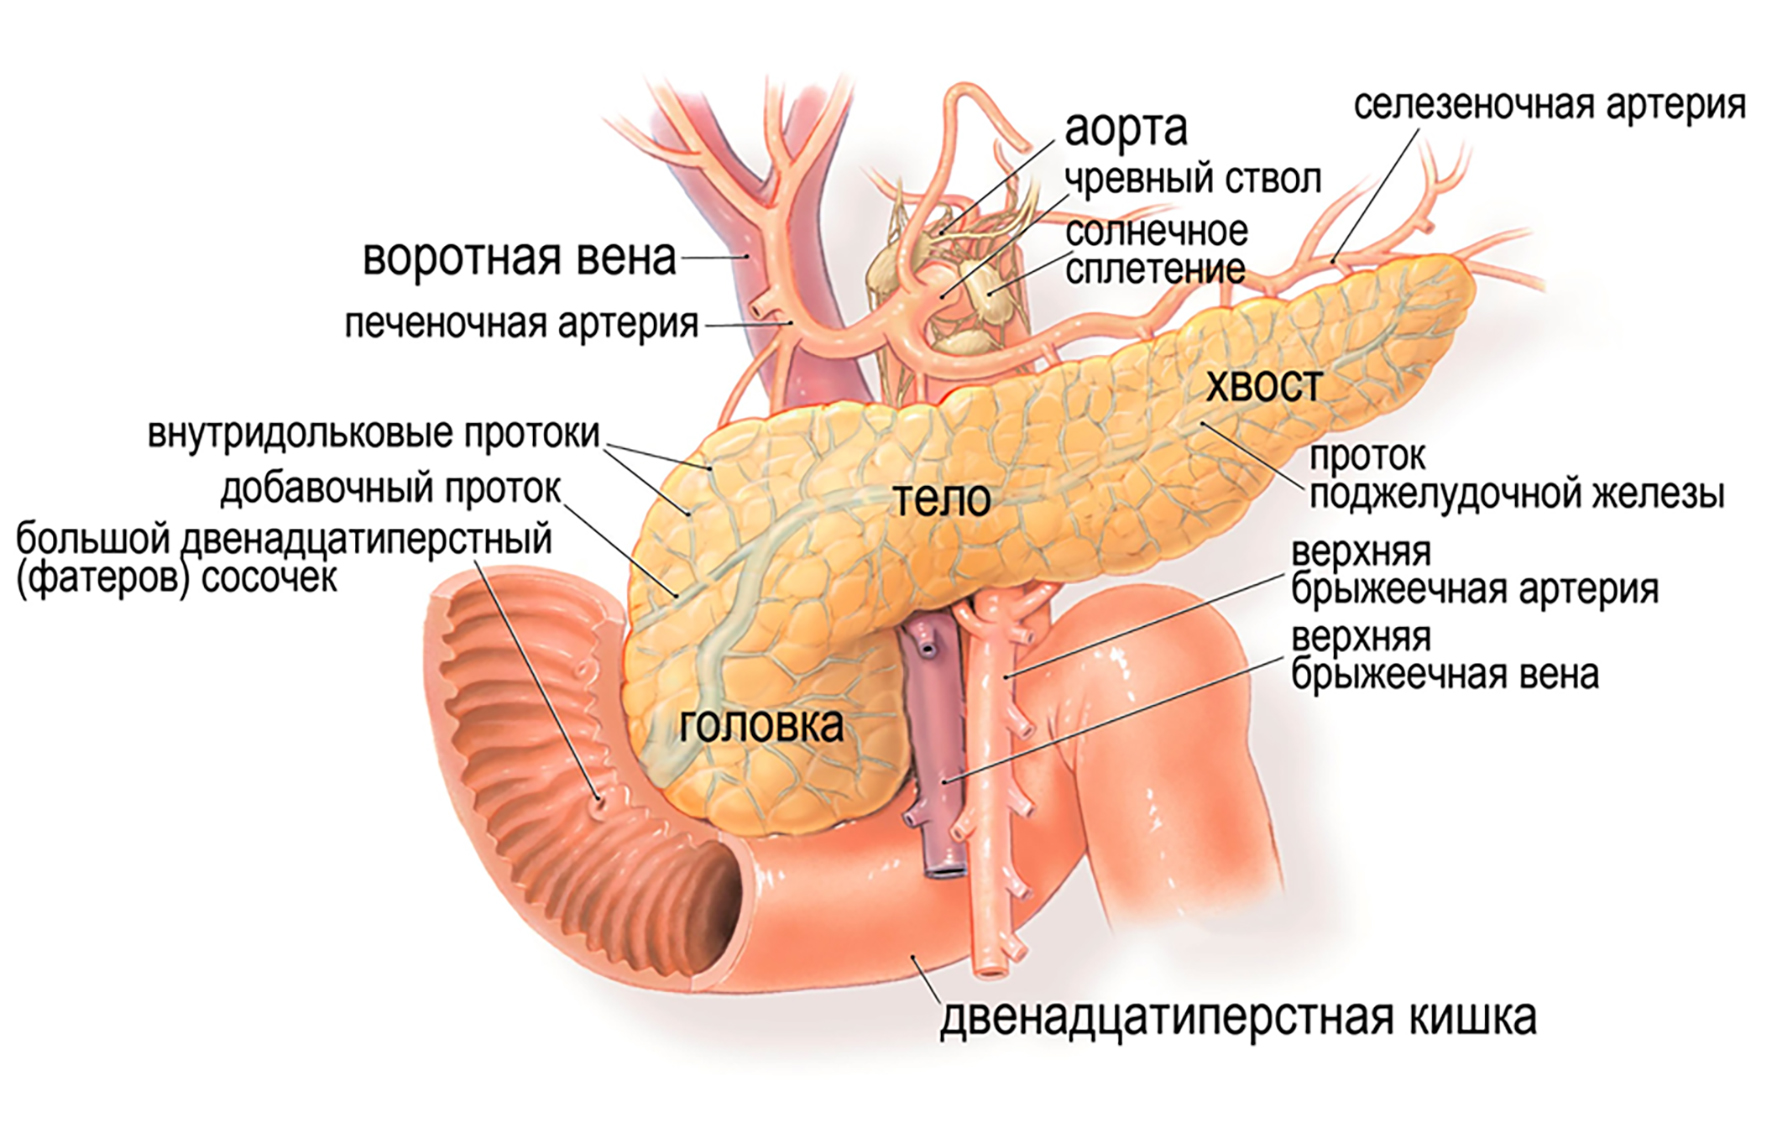

УЗИ диагностика кольцевидной поджелудочной железы: что важно знать